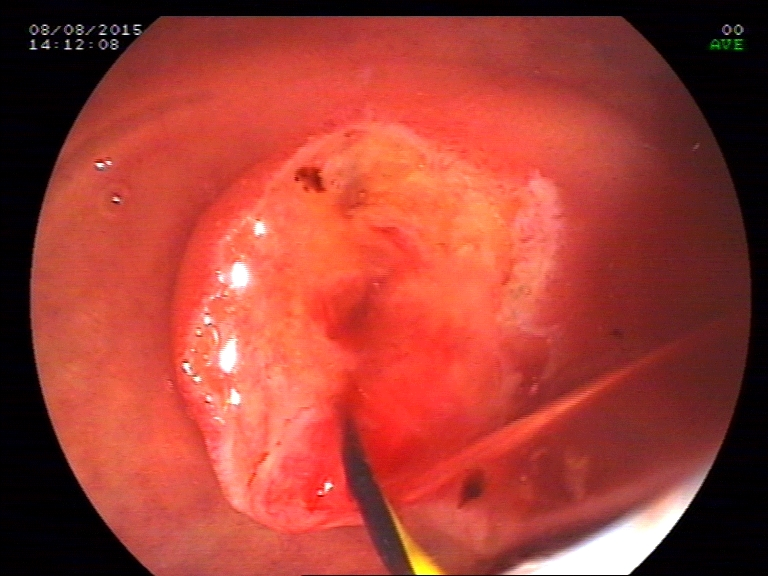

ERCP was done to remove the stone from the bile duct.Patient was sent bacl for laproscopic cholecystectomy and advised to come for removal for stent removal, a month later.